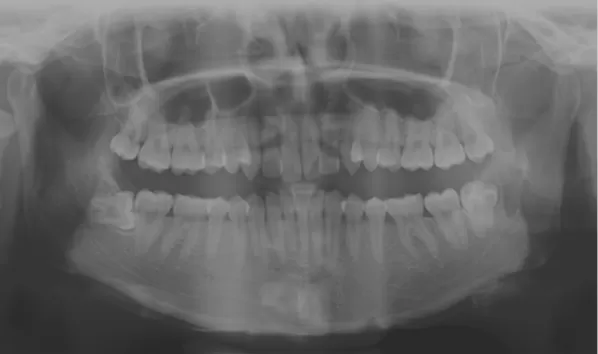

Rayons X avant le traitement

[Radiographie panoramique/Céphalogramme latéral]